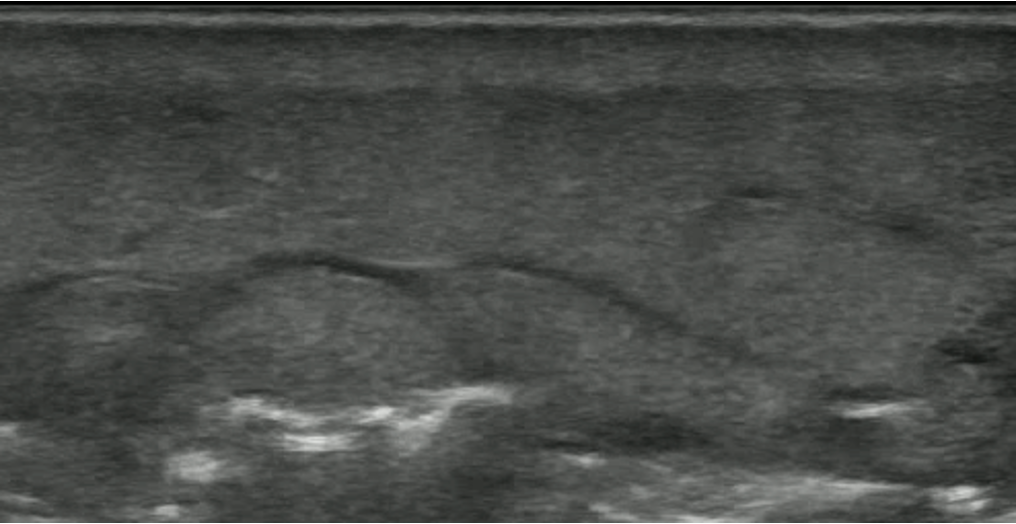

POCUS Images

• Medial Thigh Soft Tissue

POCUS Interpretation

• Cobblestoning: Fat lobules separated by hypoechoic fluid (Blue arrows)

• Seen in any cause of tissue edema

cobbllstoning

• Hyperechoic lines (Red Arrow) with dirty white shadowing (Green Arrows)

• This Finding is suggestive of gas within the Soft Tissues

hyperechoiclines

• Fluid Stripe along Fascial Plane

fluid stripe